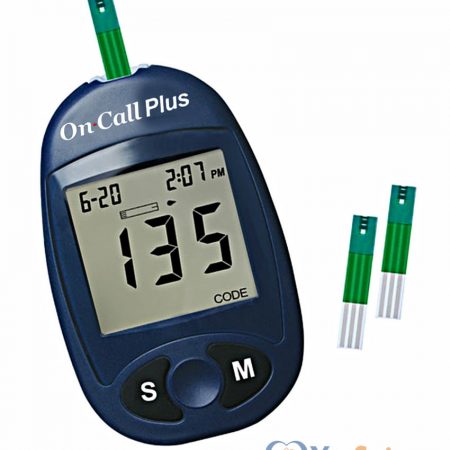

Máy đo đường huyết On Call Plus sử dụng men glucose oxidase làm chất phản ứng trong que thử. Loại men này chỉ phản ứng với đường glucose có trong máu, do vậy kết quả đo có độ chính xác cao.

649.000 ₫Brand : Acon - Mỹ -